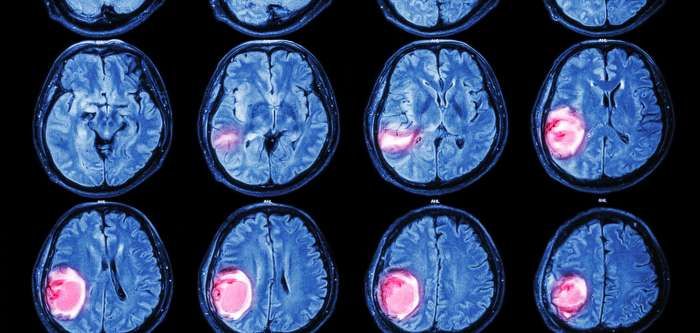

33+ Aggressive Brain Cancer Prognosis Images. For example, the most aggressive type of. Brain tumors vary in their growth rate and ability to cause symptoms.

Brain tumors vary in their growth rate and ability to cause symptoms.